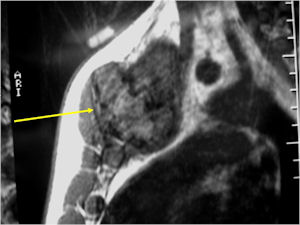

Plain X-rays:

- Geographic, circumscribed lesion usually around 5cm in size.

- There may be expansion of bone, cortical thinning and cortical breakthrough. A soft tissue mass may accompany this lesion but the soft tissue component is usually contained by the periosteum.

- The periosteum remains intact around the soft tissue component. Might need a CT scan to detect the subtle calcification (Egg Shell Rim of Calcification) associated with an intact periosteal reaction

- The lesion may be entirely radiolucent but usually shows some degree of mineralization. Mineralization may appear stippled like cartilage but do not see chondroid pathologically. Mineralization is sometimes better detected on a CT scan rather than an x-ray.

- Usually less surrounding sclerosis than an osteoid osteoma.